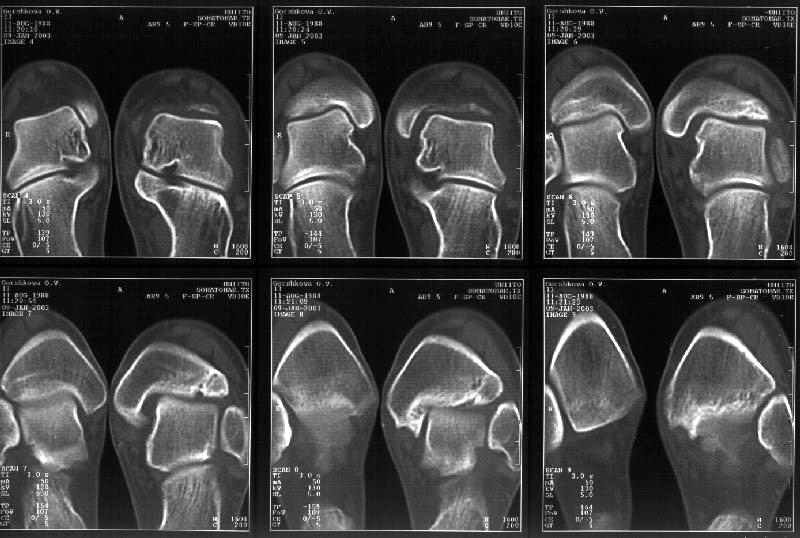

Я пометил линию перелома черной линией.

К сожалению на последних присланных срезах КТ нет более низкого, через таран, среза, который был на прежнем майле. На XR я попытался показать

стержень внутри сустава и то как он раскрывает пространство между тараном и мед. малеолом.

Сегодня пациентке сделали сравнительную КТ. А ксиальные и Фронтальные срезы приложены. Ваше мнение?

Фронтальные

Аксиальные

На КТ я попытался изобразить скромными своими способностями (А)- место перелома, (С)- нормальный суставной зазор меж тараном и тремя его маллеолами. (В)- образовавшийся в результате перелома широкий раза в три зазор, позволяющий, по-моему, сублюксацию тарана при ходьбе. В свете данных КТ, критически важных, я бы предложил вертикальную остеотомию места перелома

задне-внутренним подходом и фиксацию мед. маллеола прижатым к тарану с помощью тонкого compression screw. После этого гипсовый сапожок и немедленное расхаживание ноги.